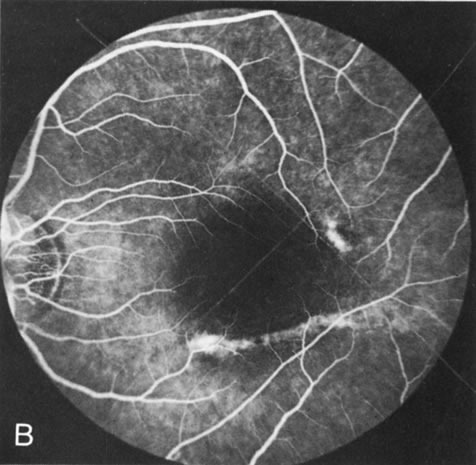

Choroideremia

In the early stages of choroideremia, before choroidal atrophy is funduscopically obvious and when the picture resembles RP, FA indicates diffuse choroidal atrophy throughout the entire retina. Only the macular area remains preserved (Fig. 4A and B).

Fig. 4. Choroideremia and choroideremia carrier. A. The choroidal atrophy in this affected male is not apparent in the fundus. B. However, the angiogram shows diffuse atrophy of the choriocapillaris with persistent visualization of the larger choroidal vessels. C. This carrier female has peripapillary choroidal atrophy and diffuse pigment mottling. D. The patchy areas of focal choroidal atrophy that occasionally occurs in carriers is evident on angiography. |